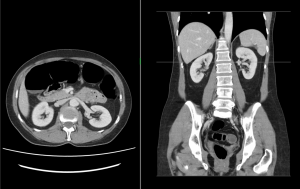

Ukázky snímků